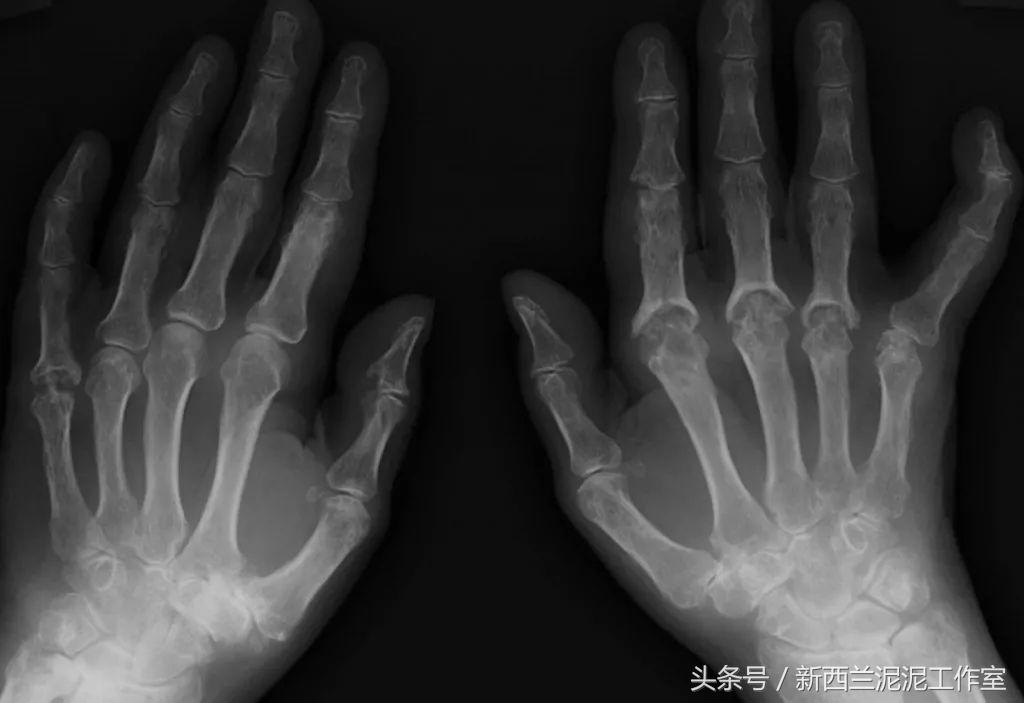

*啡吗**与*洛因海**的分子式